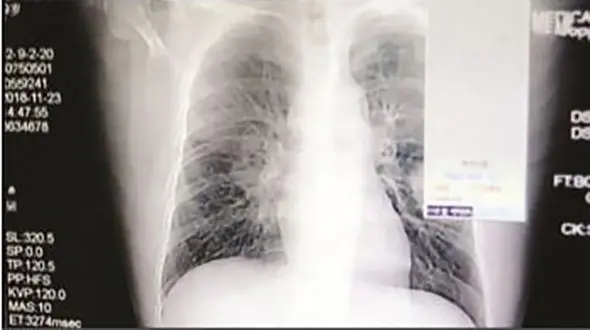

رکنا: رئیس هجدهمین کنگره بین المللی بیماریهای شایع کودکان گفت: تزریق واکسن عفونت ریه (پنوموکوک) که یک بیماری ویروسی و اخیرا شایع شده در کودکان ضروری است.

ما الان مکرر با پنومونیهای شدید مواجه می شویم که نیازمند بستریهای طولانی و اقدامات تهاجمی همچون گذاشتن لوله در قفسه سینه هستند که عوارض زیادی برای کودکان دارد و حتی میتواند باعث مرگ و میر آنها…